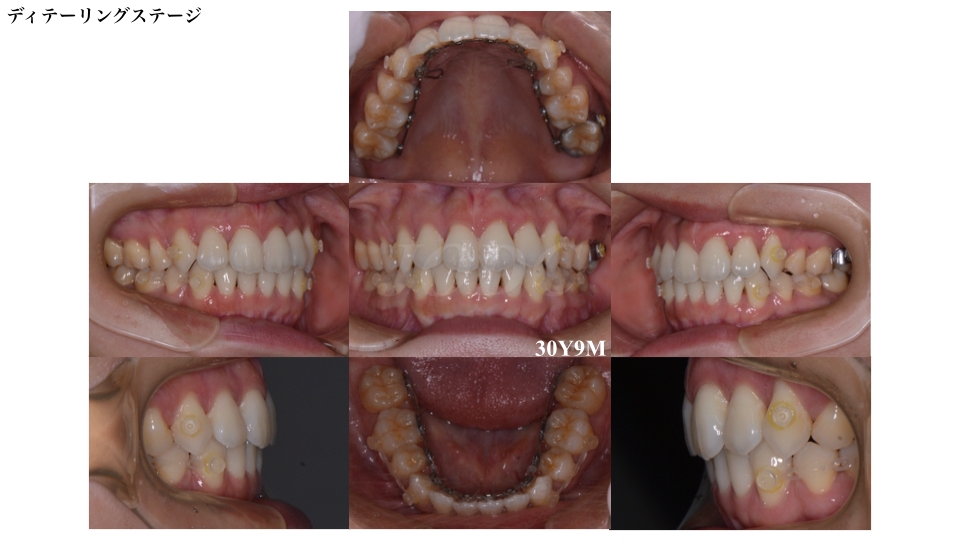

個々の歯の詳細な配列を行うディテーリングステージです。